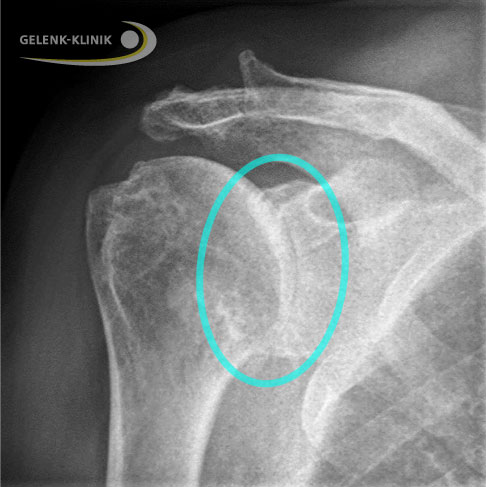

Die Zerstörung der Gelenkfläche der Schulter durch Verschleiß, Unfall oder Krankheit kann eine Schulterarthrose (Omarthrose) verursachen. Das Röntgenbild zeigt den vollständigen Verlust des Gelenkspalts (Markierung). © Gelenk-Klinik

Die Implantation einer Schulterprothese ist sinnvoll, wenn der Gelenkverschleiß (Schulterarthrose) oder die Schädigung des Schultergelenks so weit fortgeschritten sind, dass konservative Therapien und gelenkerhaltende Operationen der Schulter erfolglos bleiben. Vor allem der Leidensdruck der Betroffenen durch die chronischen Schulterschmerzen und die zunehmende Einsteifung des Schultergelenks sind wichtige Indikatoren für den richtigen Operationszeitpunkt.